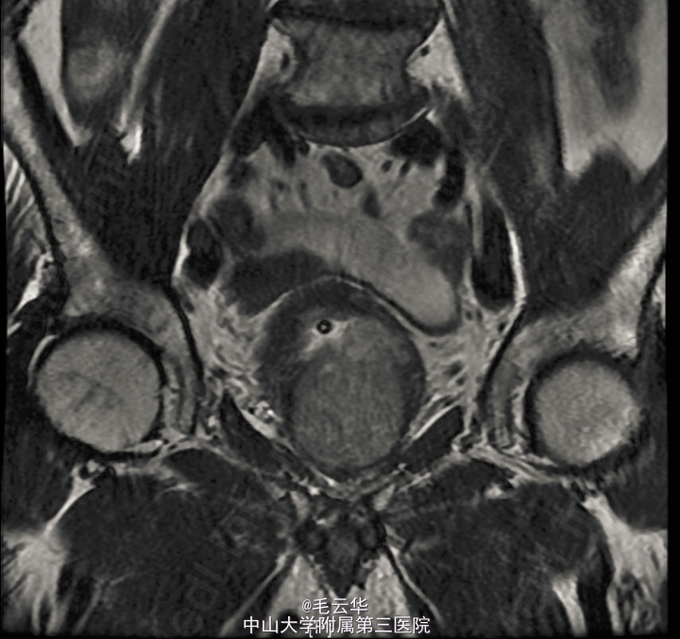

入院诊断:急性尿潴留,前列腺增生症 鉴别诊断:1.前列腺癌 2.膀胱颈纤维化 3尿道狭窄 4 神经源性膀胱 入院完善相关检查,盆腔MR示前列腺增生;左侧外周带T2WI信号降低,恶变待排,建议活检。B超引导下证实前列腺癌Gleason3+3=6分。行腹腔镜下前列腺癌根治术。术后病理示前列腺腺癌(Gleason评分:3+3=6分),闭孔淋巴结未见癌。